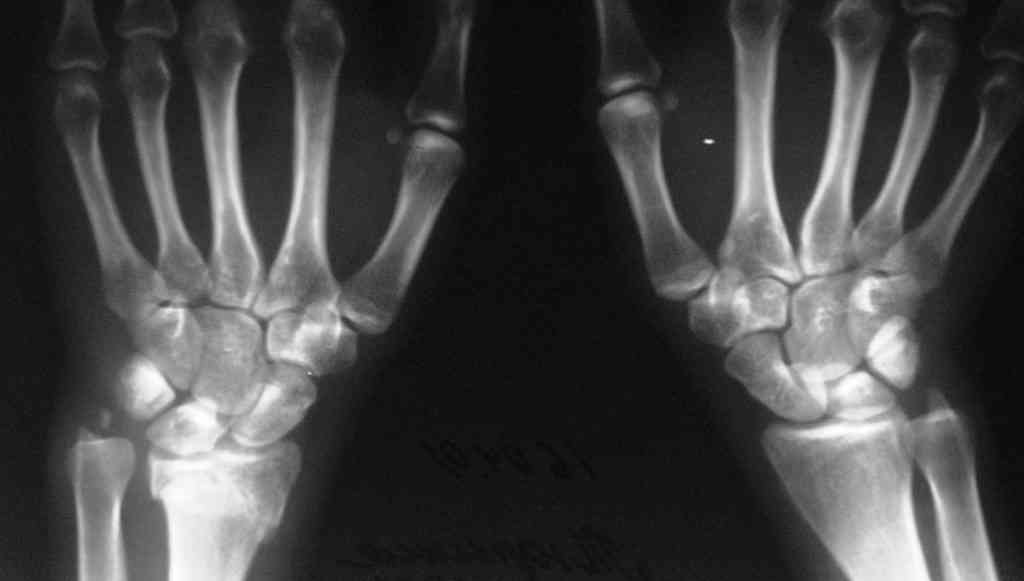

Судя по показанным Рг граммам, очевиден посттравм. артроз лучезапястного сустава, проблема дистального радиоульнарного сочленения(TFCC).

Угол наклона лучевой фасетки в норме в пределах 10-15 градусов, на представленном боковом снимке -может быть чуть больше 15градусов. Выполнив

разгибательную остеотомию луча, ты поставишь фасетку в нейтральное положение и таким образом увеличится угол разгибания , но уменьшится сгибание. По сути, амплитуда движений останется такой же.

Судя по состоянию суставных поверхностей луча - никакая остеотомия объём флексии-экстензии заметно не увеличит. Мне кажется, что при отсутствии болевого синдрома лучевую кость лучше оставить как есть.

Наряду с предложенной выше клиновидной остеотомией луча возможна моделирующая резекция локтевой на уровне псевдоартроза, это вернет подвижность в луче-локтевом суставе не добавляя артроза в кистевом, тк он там уже есть.